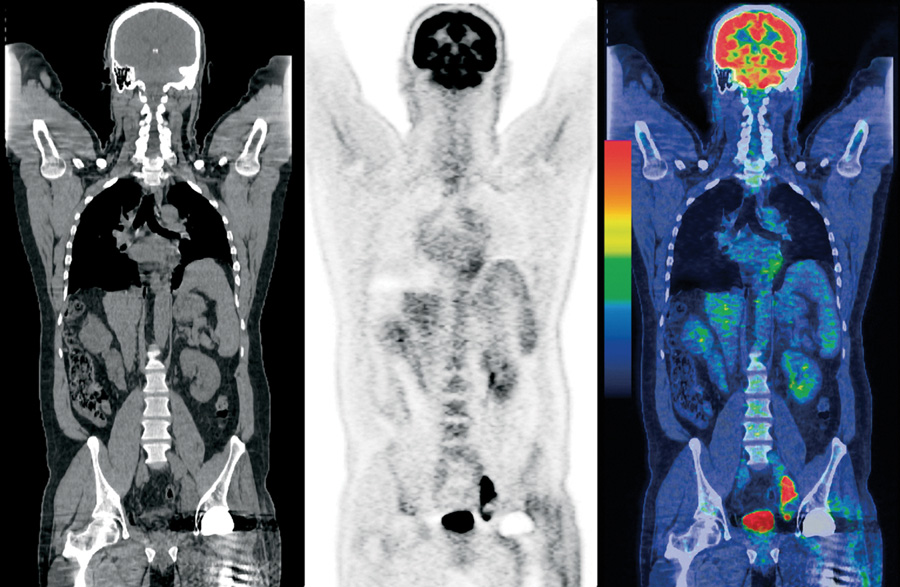

O PET-CT combina duas tecnologias, formando um exame híbrido: a tomografia por emissão de pósitrons (PET) e a tomografia computadorizada (CT). A fusão dessas técnicas permite ao médico enxergar a estrutura anatômica e o funcionamento metabólico das células quase ao mesmo tempo.

No PET, utiliza-se um radiofármaco, geralmente o 18F-FDG, que é um tipo de açúcar marcado com uma substância radioativa (fluor-18). Esse composto é injetado na veia do paciente. As células do corpo absorvem a substância, mas as células cancerosas, por serem mais ativas, a consomem em maior quantidade. A partir daí, o equipamento de PET detecta a radiação emitida e monta imagens mostrando as áreas de captação elevada.

Já o CT faz centenas de cortes radiográficos finíssimos e monta imagens muito detalhadas das estruturas internas, localizando precisamente onde está aquela atividade alterada vista pelo PET.